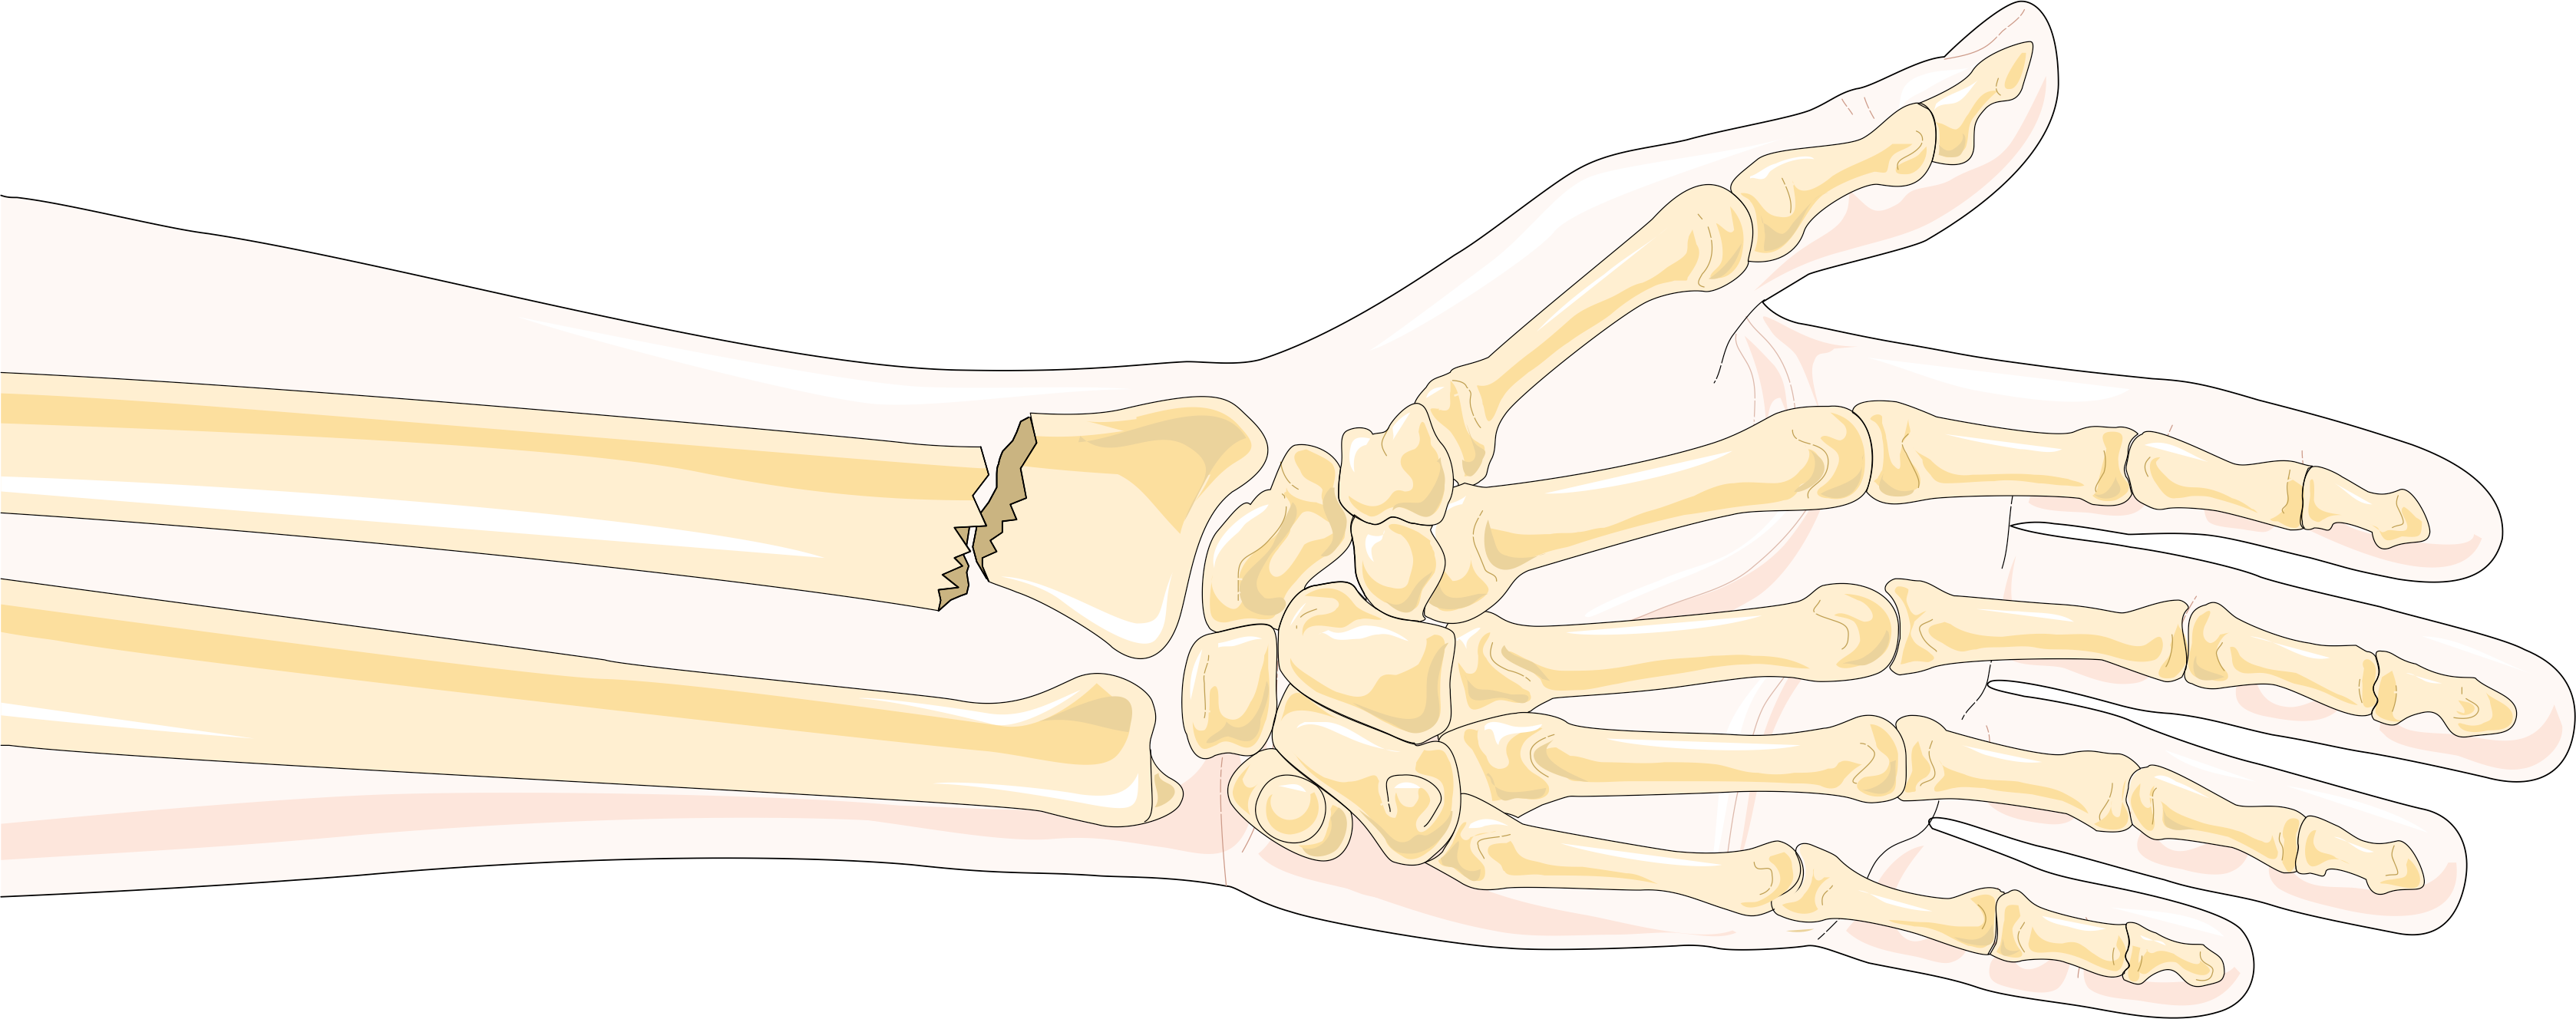

노뼈와 관련된 특정 골절 유형으로는 에섹스-로프레스티 골절, 갈레아지 골절, 콜레스 골절, 스미스 골절, 바르톤 골절 등이 있다.

- 콜레스 골절: 손목과 손의 배측(후방) 변위가 있는 원위부 노뼈 골절

- 스미스 골절: 손목과 손의 굴측(복측) 변위가 있는 원위부 노뼈 골절

- 바르톤 골절: 요골 수근 관절의 탈구와 함께 원위부 노뼈의 관절내 골절